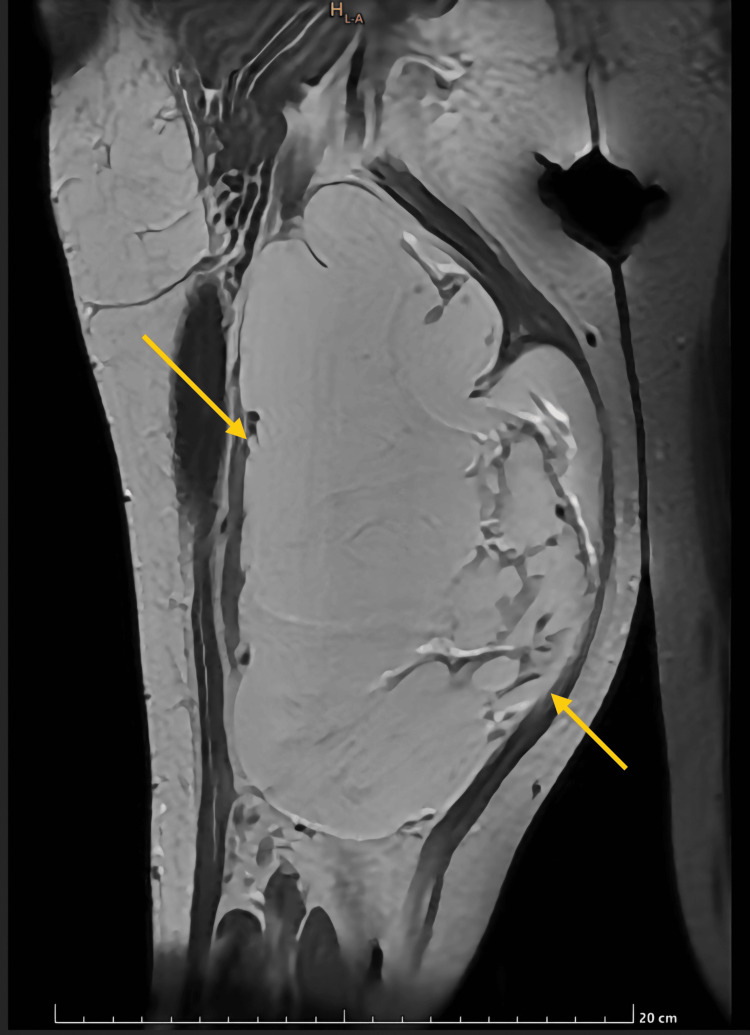

Hallazgo radiológico característico

3) Imagen

Los hallazgos de imagen del UPS son inespecíficos y reflejan su naturaleza de sarcoma de alto grado: gran tamaño, márgenes infiltrativos, heterogeneidad y necrosis. La RM es la técnica de elección para la estadificación local; la TC torácica es obligatoria para descartar metástasis.

3.2 Resonancia magnética (RM)

- 🔹 Morfología: Masa bien delimitada pero no encapsulada, localizada profundamente al fascia, a menudo en contacto o infiltrando grupos musculares. Tamaño grande (5-20 cm) al diagnóstico .

- 🔹 T1: Señal isointensa o ligeramente hipointensa respecto al músculo. Las áreas de hemorragia subaguda pueden mostrar señal hiperintensa.

- 🔹 T2: Señal marcadamente heterogénea, predominantemente hiperintensa. Las áreas de necrosis y mixoide son muy hiperintensas; las zonas de fibrosis e hipercelularidad son hipointensas. Hasta el 25% corresponden al subtipo mixoide (antes mixofibrosarcoma) .

- 🔹 Hallazgos característicos:

- 🔹 "Fibrous septum sign": Tabiques internos hipointensos en T2 que realzan tras contraste. Refleja bandas fibrosas que dividen el tumor en lóbulos. Altamente sugestivo .

- 🔹 "Tail sign" (signo de la cola): Prolongación lineal del tumor a lo largo de fascias o septos intermusculares. Indica infiltración microscópica más allá del margen aparente .

- 🔹 "Pseudocapsule sign": Anillo periférico hipointenso que no constituye una cápsula verdadera (infiltración microscópica presente).

- 🔹 Edema peritumoral: Frecuente, visible como halo hiperintenso en T2/STIR alrededor del tumor.

- 🔹 T1 con contraste: Realce intenso y heterogéneo de los componentes sólidos. Las áreas de necrosis no realzan. El patrón de realce puede ser periférico o en "panal" .

- 🔹 Difusión (DWI): Restricción en áreas celulares (bajo ADC). Útil para guiar biopsia hacia zonas de mayor grado.